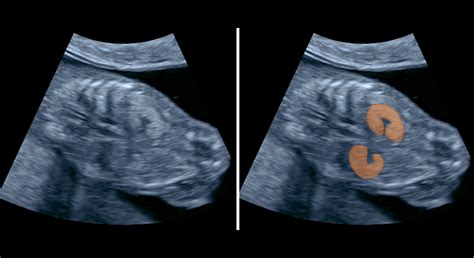

Na konci 12. týždňa tehotenstva sa plod začína podobať na človeka. Má vyvinuté prsty na rukách a nohách, tvár s očami a ústami a vnútorné orgány sú už na svojom mieste. Pohlavie plodu je už určené, hoci ešte nie je zreteľne viditeľné na ultrazvuku.

Medzi 16. a 24. týždňom tehotenstva matka zvyčajne začína pociťovať prvé pohyby dieťaťa. Tieto pohyby sú spočiatku jemné a pripomínajú bublinky alebo šteklenie. Okolo 20. týždňa tehotenstva je zvyčajne možné určiť pohlavie dieťaťa na ultrazvuku.